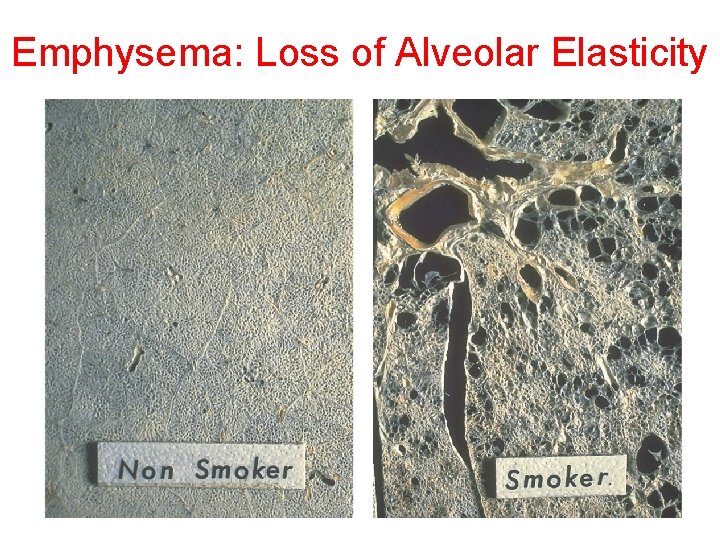

Emphysema: Loss of Alveolar Elasticity